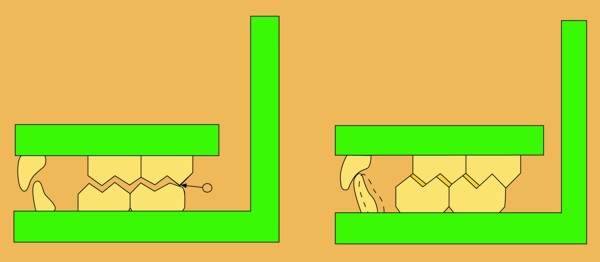

Abstract: Las fuerzas anterógradas traumáticas son en general las causantes de fracturas radiculares en el sector anterior de la boca. Desarrollo: El paciente se presenta a la consulta , con la fractura de una funda de porcelana inyectada en la zona cérvico palatina, solicitando simplemente la reparación en boca para evitar rozamientos linguales. Dicha funda con un perno colado en oro y su correspondiente endodoncia, habían sido realizadas en mi clínica varios años atrás, con un «aparente éxito total». Radiograficamente, se encuentra una fractura radicular cercana al tercio gingival Observada la oclusión de las piezas anteriores, podemos ver que el vínculo ideal de Acoplamiento, no se cumple, habiendo una relación de franco contacto la que ha provocado la fractura. Llevando al paciente a Oclusión en Relación Céntrica, podemos ver el espacio a nivel anterior, correspondiente a la centricidad mandibular. En esa misma posición , es dable percibir una faceta parafuncional mesial del primer premolar superior… …que antagoniza con una faceta parafuncional distal del canino inferior… ..constituyendo un plano inclinado que provoca la antelación mandibular o Discrepancia Horizontal, fracturando la raiz del incisivo central. Extraida la porción coronal de la raiz, pensamos en la realización de un Implante Inmediato, a pesar de la presencia de una fístula dado que se trataba de un central, decisión que obtuvo éxito implantario mas no estético, según veremos luego. Era fundamental conservar lo mas posible las tablas óseas, que de hecho había perdido la porción cervical Realizamos una incisión que conservara las papilas de las piezas adyacentes. Realizamos la exodoncia mediante un instrumento construido «ad hoc» que denomino: Con lo que obtenemos la preservación «ad integrum» de las corticales peridentarias remanentes. Instalamos entonces un implante T.B.R. de 15 mm de largo por 4 mm de diam. con cuello de zirconio de 3,5 mm …quedando tres espiras sin hueso por vestibular, producto de la tabla perdida, Incidimos el periostio a nivel apical del colgajo para obtener mayor paño quirúrgico, y legramos un bolsillo palatino sin incisiones de descarga, para la inserción de la membrana. Suplementamos la carencia ósea vestibular con «BIOSS» …e instalamos una membrana reabsorbible «BIOGUIDE» , que fijamos con el mismo implante, y calzamos por palatino. Suturamos Instalamos nuestra provisional previamente confeccionada, sobre un abuttment de titanio. Y controlamos radiograficamente Pasadas tres semanas del retiro de los puntos, observamos una cicatrización alta que nos muestra el anillo de zirconio del implante. ……………………………………………….. Transcurridos tres meses preparamos una nueva cirugía, dirigida a instalar un injerto autólogo de conectivo en el área del anillo, con un nuevo desplazamiento del colgajo vestibular. Tomamos tejido conectivo del paladar a nivel de los premolares, mediante una incisión mucosa «en libro», y disección del conectivo subyacente. Lo posicionamos en vestibular del anillo de zirconio y lo fijamos mediante sutura Y semanas después nos encontramos con un nuevo fracaso de orden estético. ……………………………………………….. En la actualidad, el caso esta estable , aún con su funda provisional, a la espera de un nuevo intento plástico, mediante Injerto Libre de Encia. ………………………………………………….. ESQUEMA MECÁNICO DEL FENÓMENO …que además de los hechos mostrados en el caso presentado, frecuentemente provocan en el sentido antero posterior los fenómenos de DISPERSIÓN ,en el maxilar superior…y de APIÑAMIENTO en el maxilar inferior. CONCLUSIONES: Además del rigor académico que nos convoca… esta; nuestra casa…nos otorga la confianza que solo da el saber que estamos siempre entre amigos, que cada vez son más. Por tanto es que debo decir: YO fui el responsable de dicha fractura… …porque… …..que hubiera sucedido si hubiera hecho todo el trabajo implantario sin ajustar previamente su oclusión? Seguramente a esta altura del caso…también hubiera fracasado el implante. Siempre decimos que se aprende de los errores más que de los aciertos, y Dr. Carlos A. Acuña Priano

Con una Oclusión Mutuamente Compartida lograda mediante un simple Ajuste Oclusal por sustracción en sus Puntos Prematuros, y por adición en sus contactos caninos, realizados por supuesto previamente a la implantación.

Fig .38(Pié de foto: Punto Prematuro de Contacto)

Fig.39(Pie de foto: Dispersión y Apiñamiento)